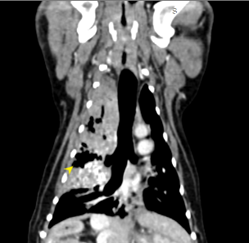

狗狗 肺臟腫瘤 Pulmonary carcinoma

持續數月的咳喘 他院懷疑心臟問題轉診來築心,經由電腦斷層掃描及胸腔採樣

確診為惡性腫瘤,由於腫瘤已經擴散不適合外科手術,主人最後決定使用化療延長壽命